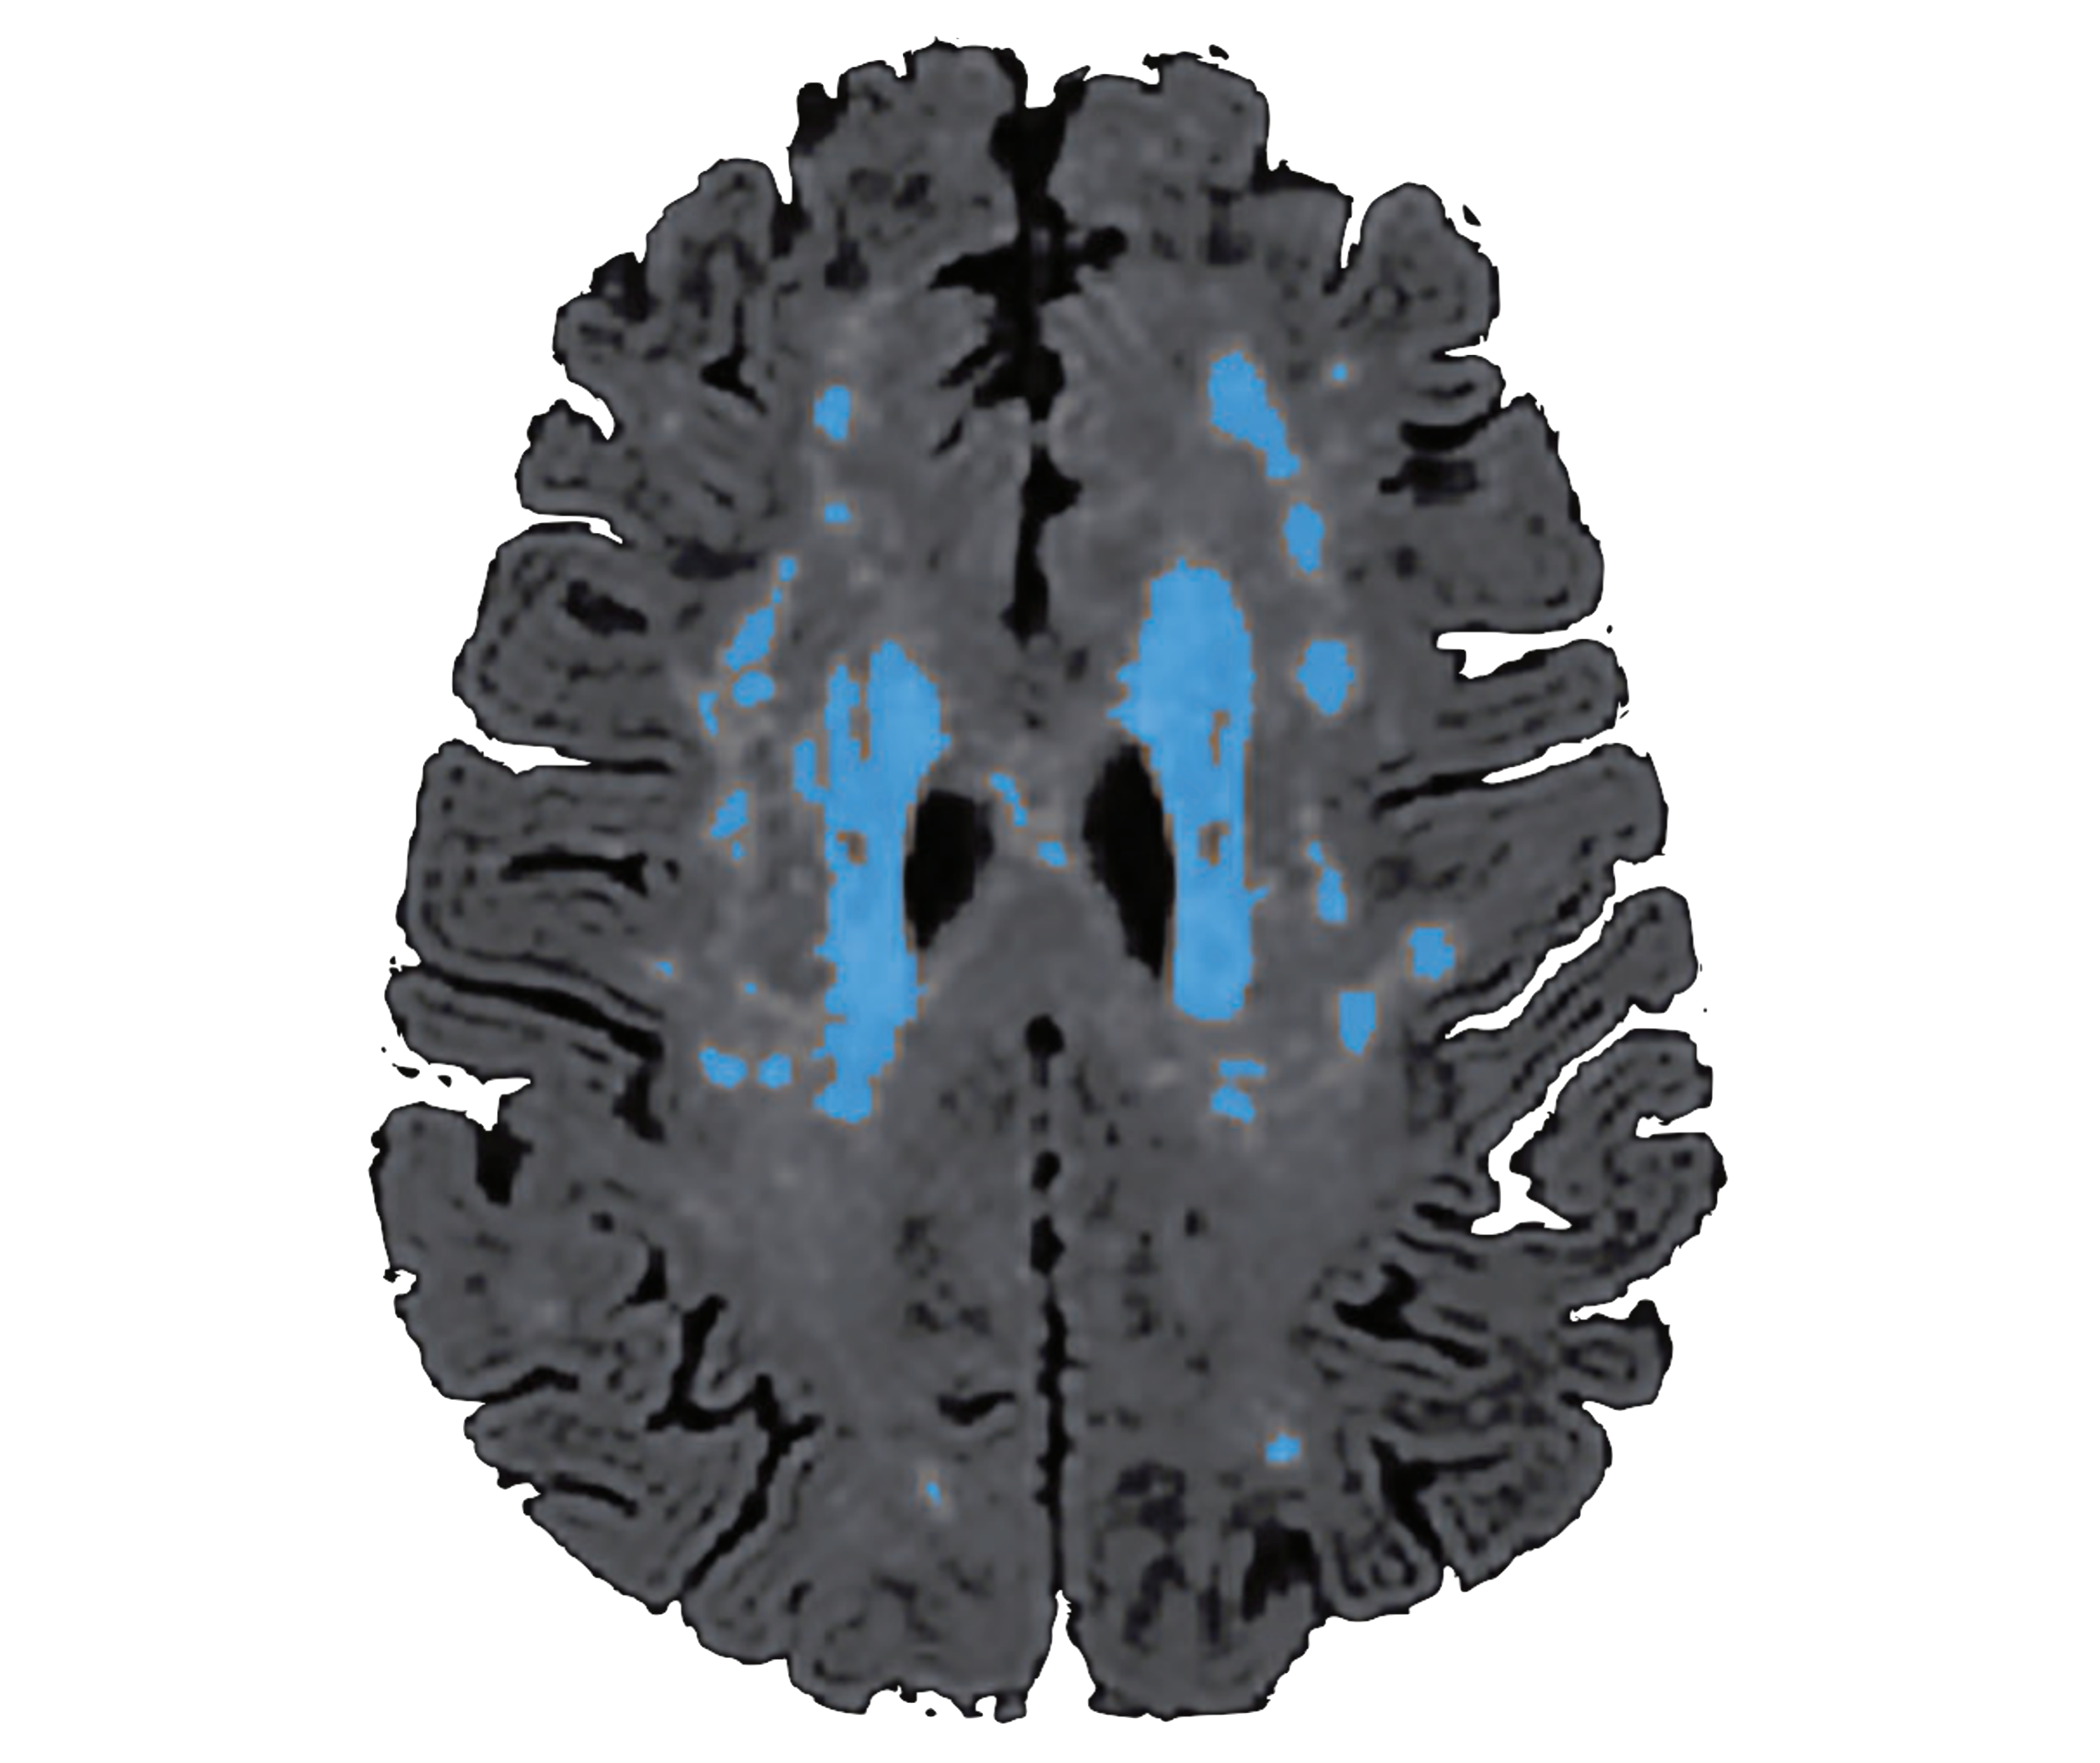

Lesion quantification toolkit

The lesion quantification toolkit (LQT) is a publicly available software package for quantifying the probabilistic impacts of focal brain lesions on structural connectivity.